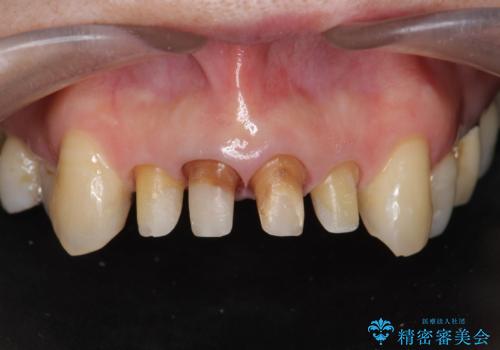

歯茎の黒ずみがきになる 前歯の見た目を改善したい

- クラウン周りの黒ずみが気になり、審美性の改善を求めて来院されました。

以前に治療した前歯クラウンは月日が経過することで劣化・歯肉の位置変化を引き起こし審美障害を引き起こしています。

劣化したクラウンを除去し、再発した虫歯を徹底的に除去したのち根管治療・ファイバーコア築盛を行いジルコニアクラウン製作へと移ります。